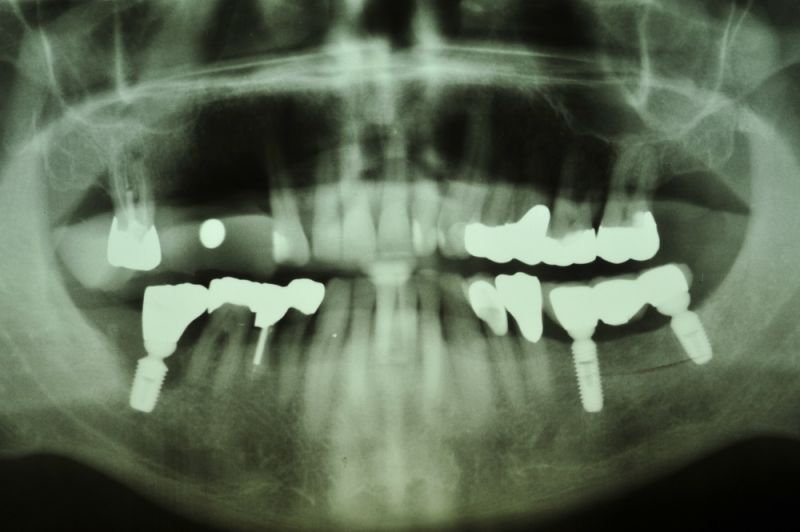

In der Zwischenzeit sind vorgeschädigte Zähne verloren gegangen und wurden zum Teil durch Implantate ersetzt.

Über eine mehrjährige Phase wurden immer wieder Laborgefertigte Dauerprovisorien eingegliedert, weil vor einer abschließenden funktionstherapeutioschen Behandlung erst noch andere Problemzonen beseitigt werden mussten.